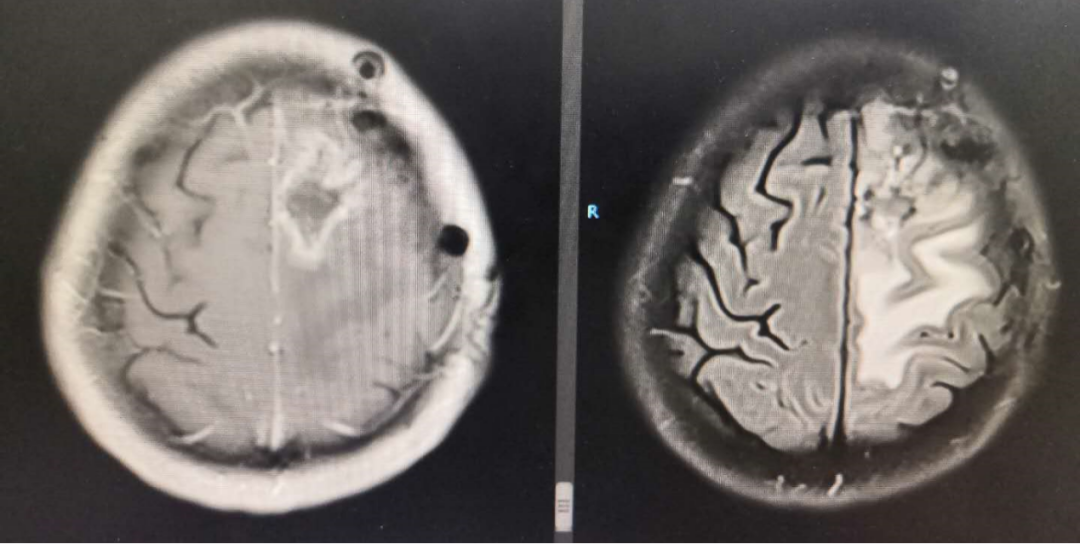

术后MRI显示术区水肿余无特殊

2020-01-06放疗后MRI

2020-4-23 MRI复查